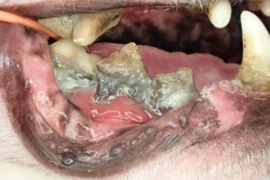

DVM, BVSc, MANZCVS, Small Animal Dentistry and Oral Surgery

Kayoko Kuroda

Dr Kayoko Kuroda graduated from the University of Queensland with a Bachelor of Veterinary Science in 2006. Since completing her degree, she has pursued her twin passions of teaching and clinical practice while working in small animal general practice around Queensland. She obtained Membership in the Australian and New Zealand College of Veterinary Scientists (ANZCVS) in Small Animal Dentistry and Oral Surgery in 2018. Dr Kuroda is currently working as a consultant at North Coast Veterinary Specialist & Referral Centre (NCVS) in Sunshine Coast, QLD and roving veterinary dentistry referral practice, Mobile Pet Dentistry, as well as a small animal general practice a few days a week in northern Brisbane, managing complex and advanced dentistry. Dr Kuroda has also been working as an educator and providing small animal dentistry lectures and workshops across Australia, including Sydney University Centre for Veterinary Education (CVE).